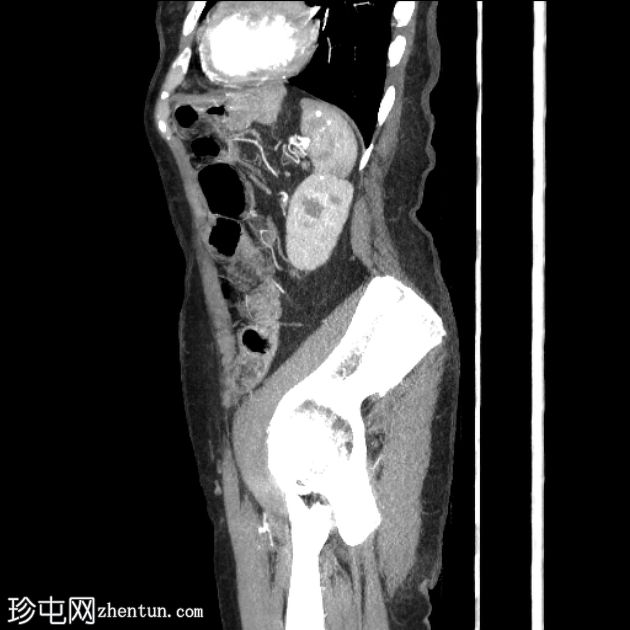

4.png

轴位增强扫描

延迟期

平扫图像显示左侧结肠脾曲处可见小憩室,伴结肠周围脂肪间隙条索状改变,提示急性结肠憩室炎。

动脉早期可见造影剂外渗,冠状位和矢状位最大强度投影(MIP)图像也可见,位于憩室炎同一部位,符合活动性出血表现。

随后的门静脉期和延迟期图像显示造影剂在结肠腔内积聚。